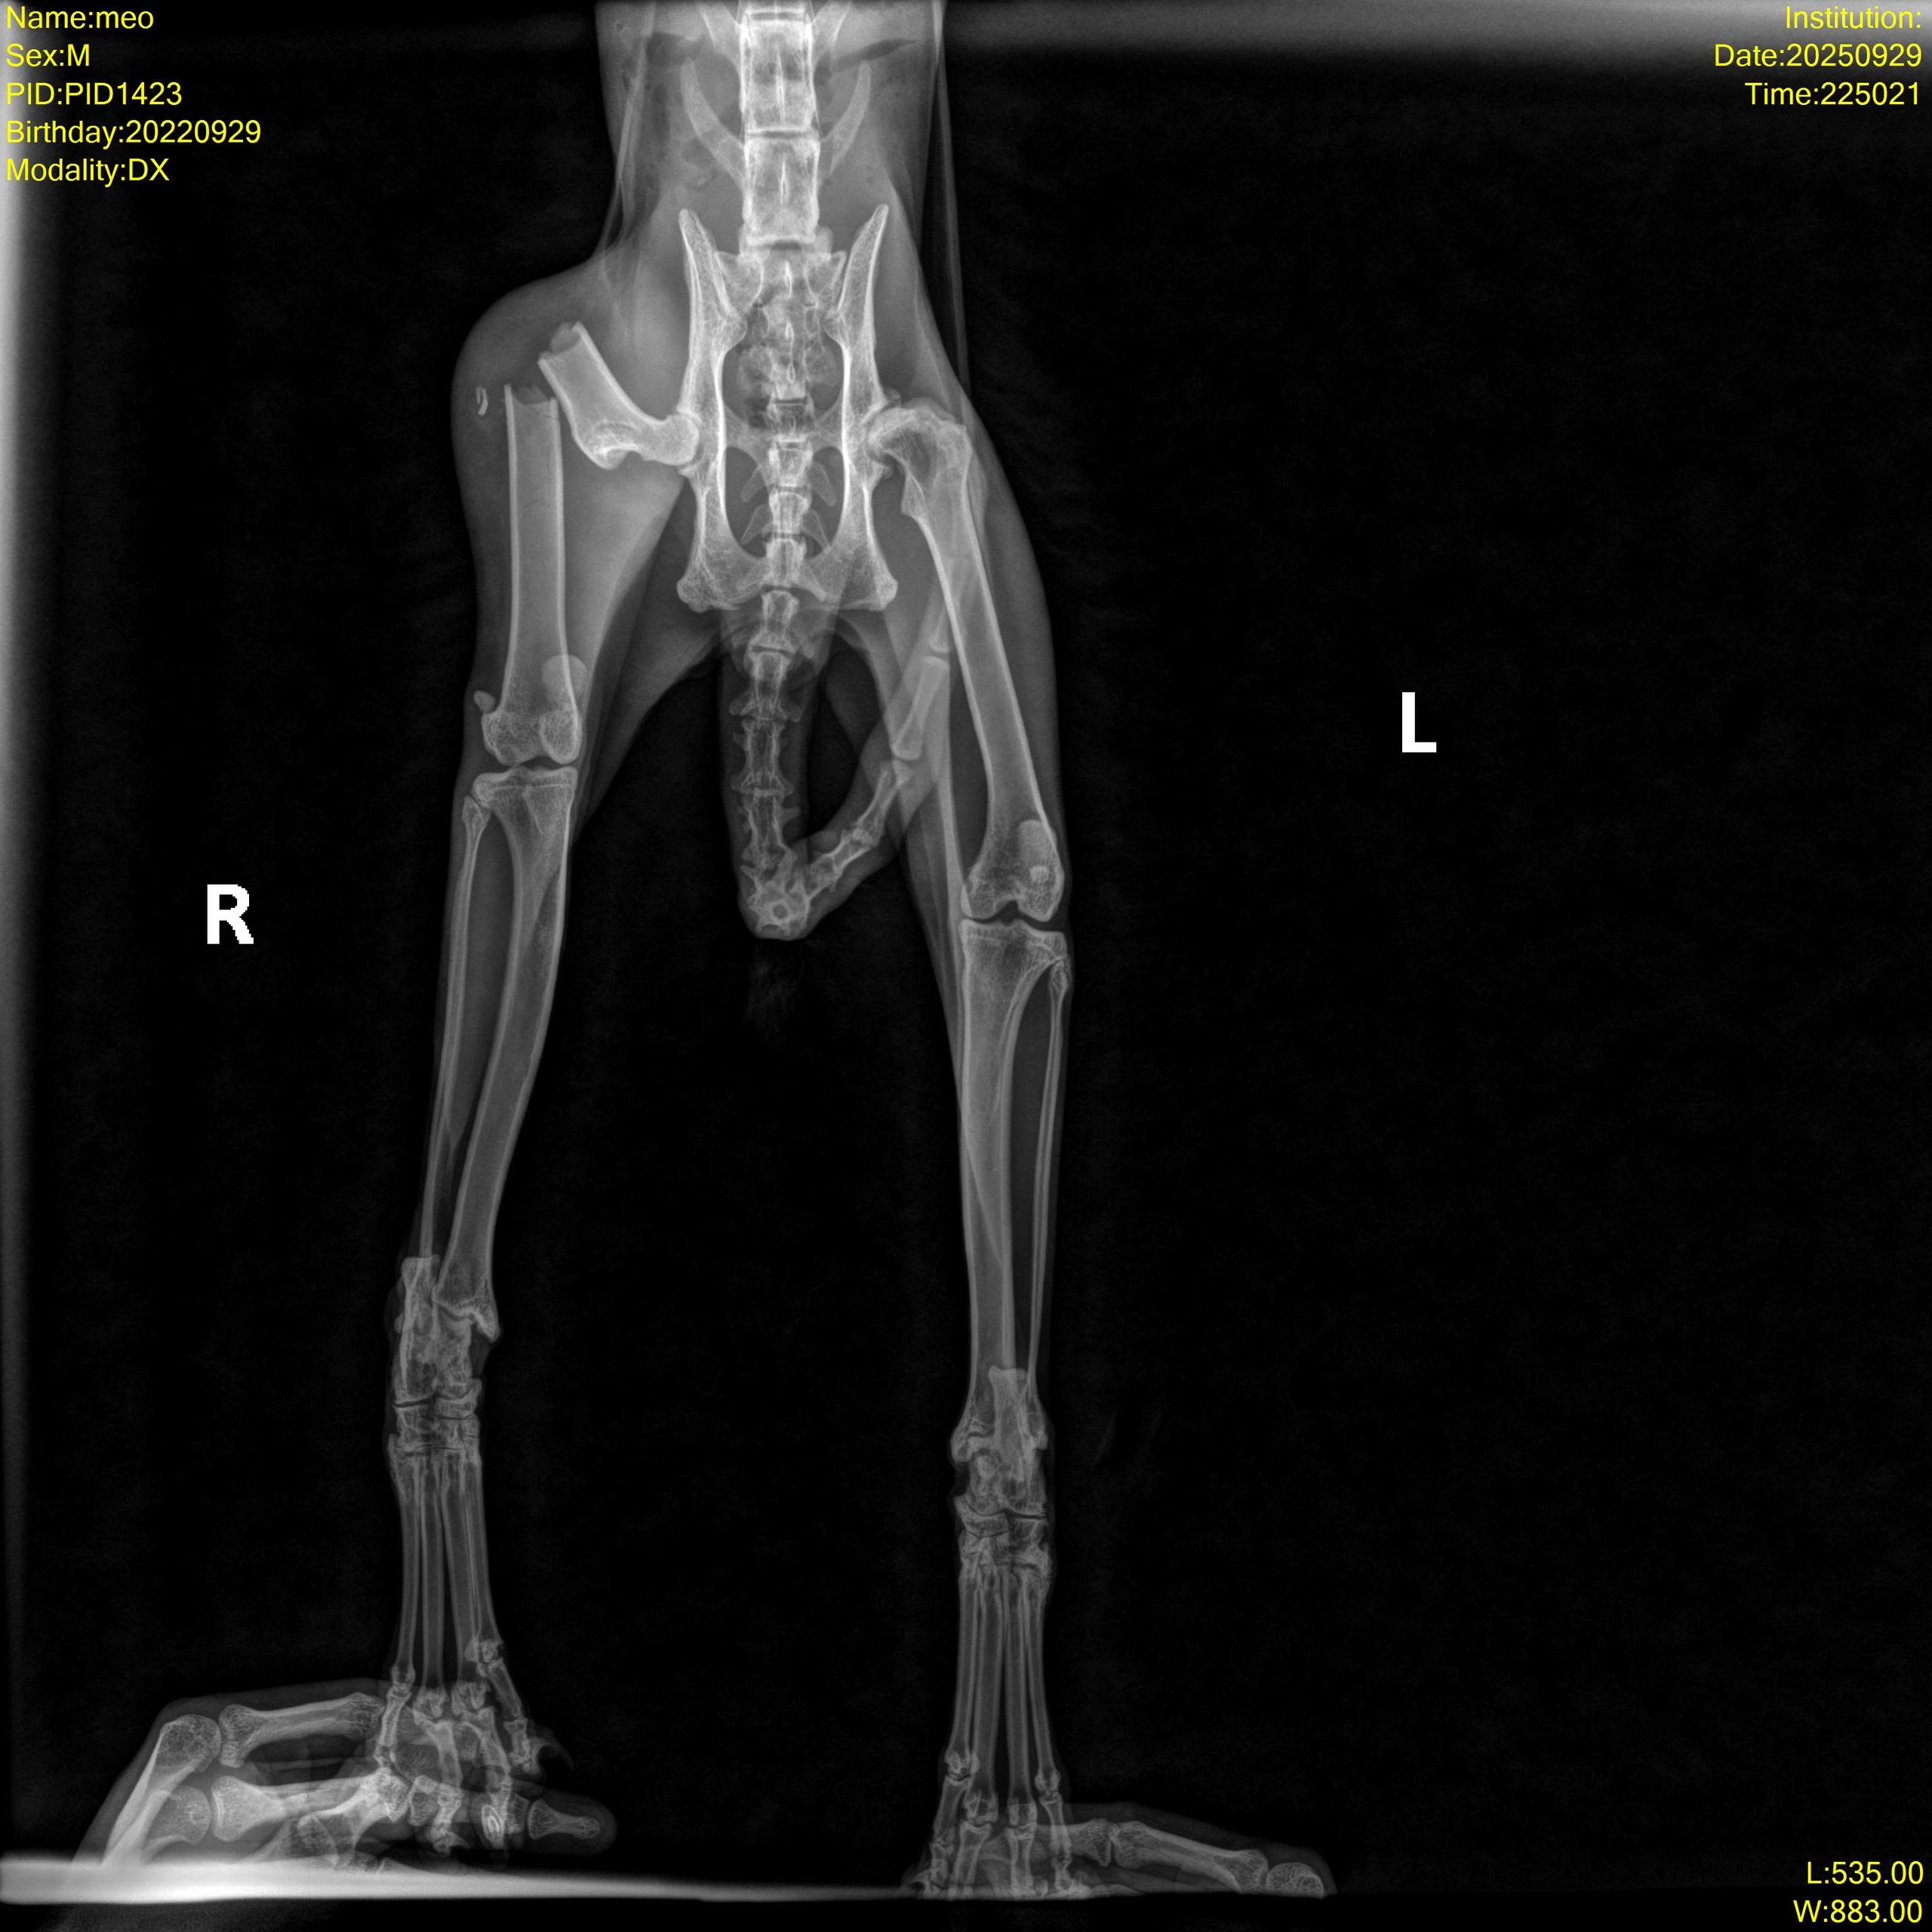

Một bạn nhặt được bé ngoài đường Mèo đực đã thiến, thể trạng gầy gò, mất nước. Niêm mạc nhợt nhạt, hai chân sau yếu, cham vào sẽ kêu đau. Trên người có vết cạo xước mất lông